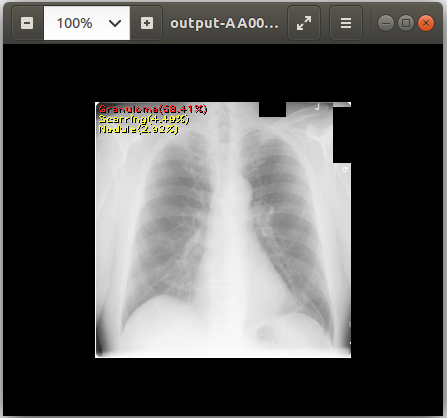

Output payload files are located under /operators/<operator name defined in the pipeline definition>/ folder. Since we triggered Chest X-ray Pipeline whose AI operator’s name is ai-app-chestxray, we can use the following command to download output files:

Then, you can see the output files using the following command:

cat output-AA0007572607123433_v2.csv # View text output eog output-AA0007572607123433_v2.png # View image output using `eog` which is an image viewer available in Ubuntu

chest_xray_example_output.png